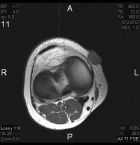

14 year old female with a tender right knee mass which has been enlarging for five months